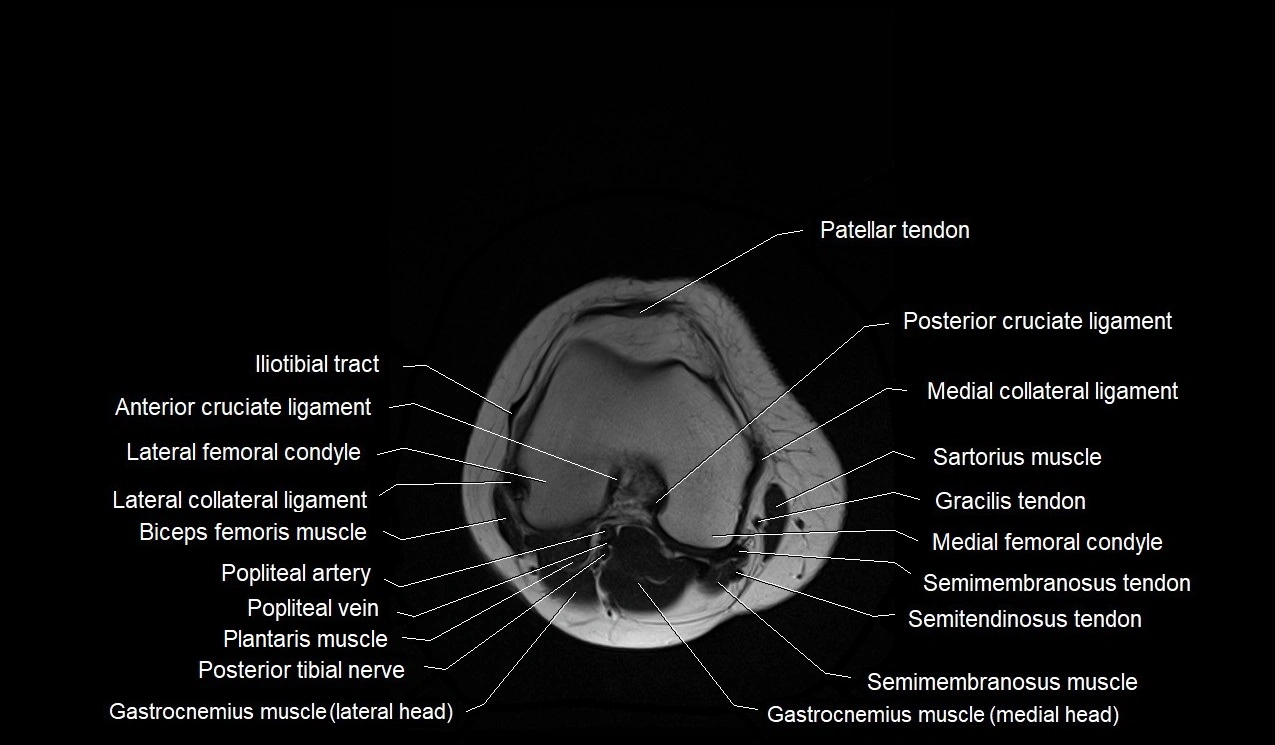

- Anterior cruciate ligament

- Iliotibial tract

- Lateral collateral ligament

- Medial collateral ligament

- Patellar tendon (patellar ligament)

- Popliteal artery

- Popliteal vein

- Posterior cruciate ligament